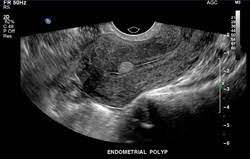

Zur Beurteilung der Eierstöcke und der Gebärmutterschleimhaut ist die Vaginalsonographie eine sichere und nicht belastende Untersuchungstechnik. Im Gegensatz dazu ist die in der gesetzlichen Vorsorge verankerte Tastuntersuchung viel weniger aussagekräftig. Die Vaginalsonographie ermöglicht das Erkennen von bösartigen und gutartigen Erkrankungen der Gebärmutter

+ Polypen